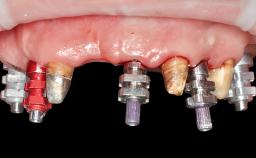

Conventional Loading of Four Implants in the Edentulous Maxilla and Restoration with a Bar-Supported Overdenture

A 64-year-old male patient was referred to the University Medical Center Groningen, The Netherlands, for dental implant treatment. The patient had been edentulous in both the maxilla and mandible for 25 years. During these 25 years, three conventional dentures had been fabricated, the most recent one being 2 years old. The patient complained of inadequate retention and stability of his maxillary and mandibular dentures. The esthetic aspect was of medium importance to the patient. His medical history was unremarkable.